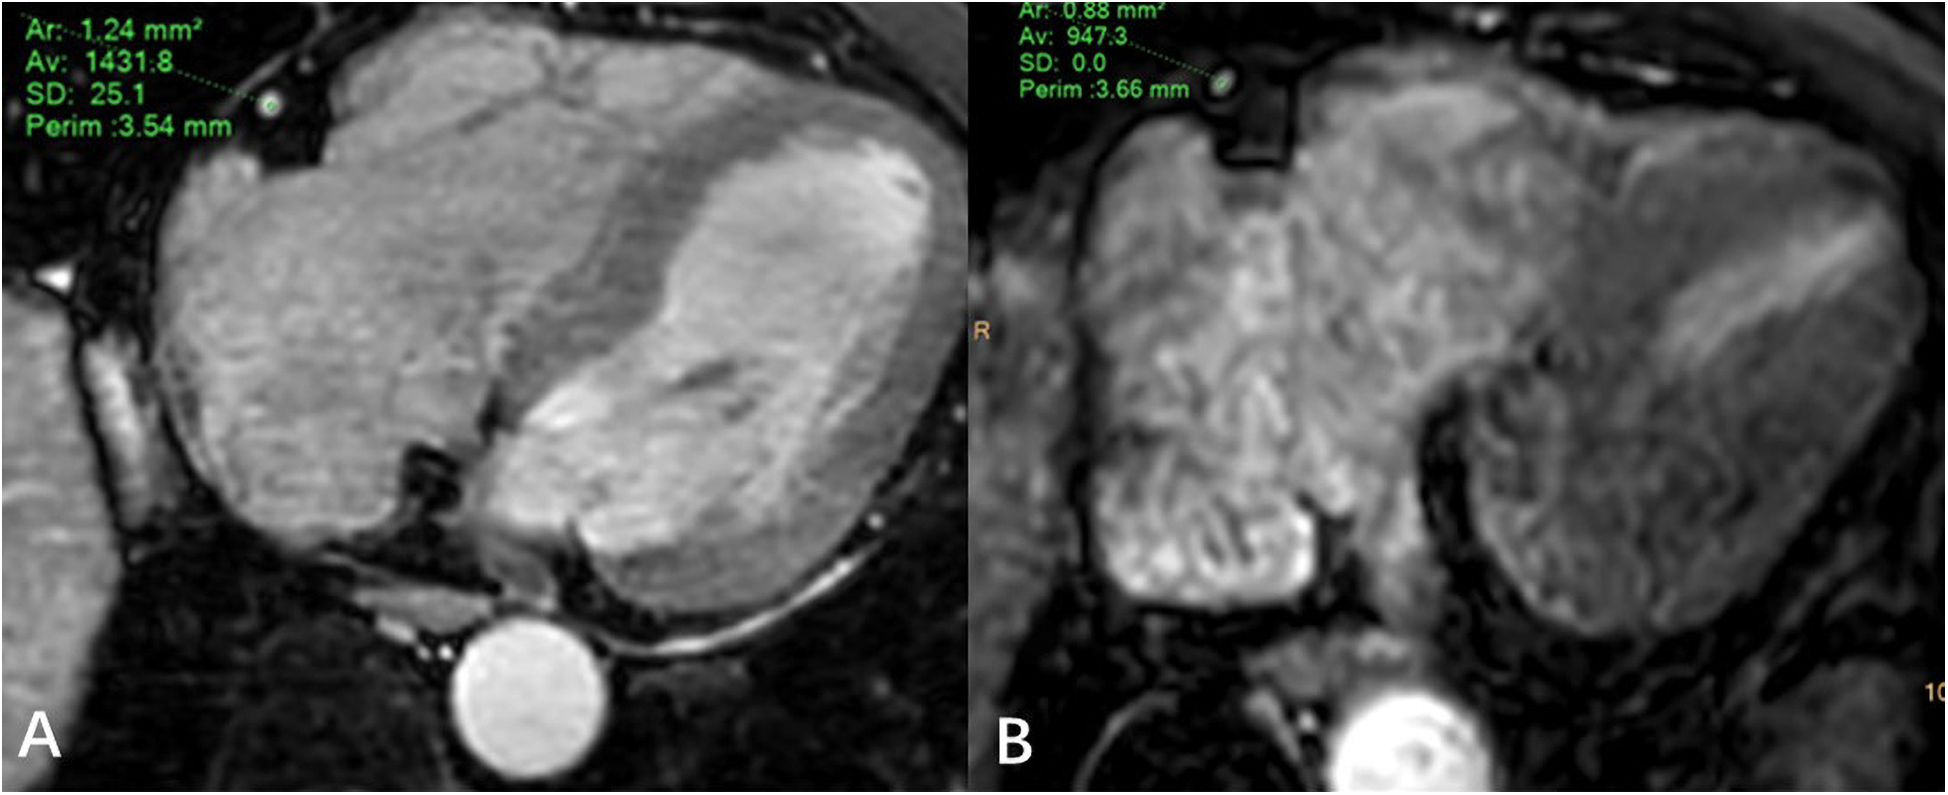

JZ and WL draw regions of interest in the axial MSG-EPI and 3D BTFE sequences. The regions of interest were slightly smaller than the lumen size, and vessels, artifacts, and stenosis areas should be avoided as much as possible ( Figure 3 ). Signal intensity (SI) and standard deviation (SD) of coronary artery segments and myocardium were measured. The signal-to-noise ratio (SNR) and contrast-to-noise ratio (CNR) of each segment of the coronary artery were calculated as follows: SNR = SIcoronary artery/SDmyocardium; CNR = (SIcoronary artery − SImyocardium)/SDmyocardium. In order to minimize the deviation of a single measurement, measurements were made three times and the average value was calculated.

Figure 3

Regions of interest example diagram in axial MSG-EPI (A) and 3D BTFE (B).